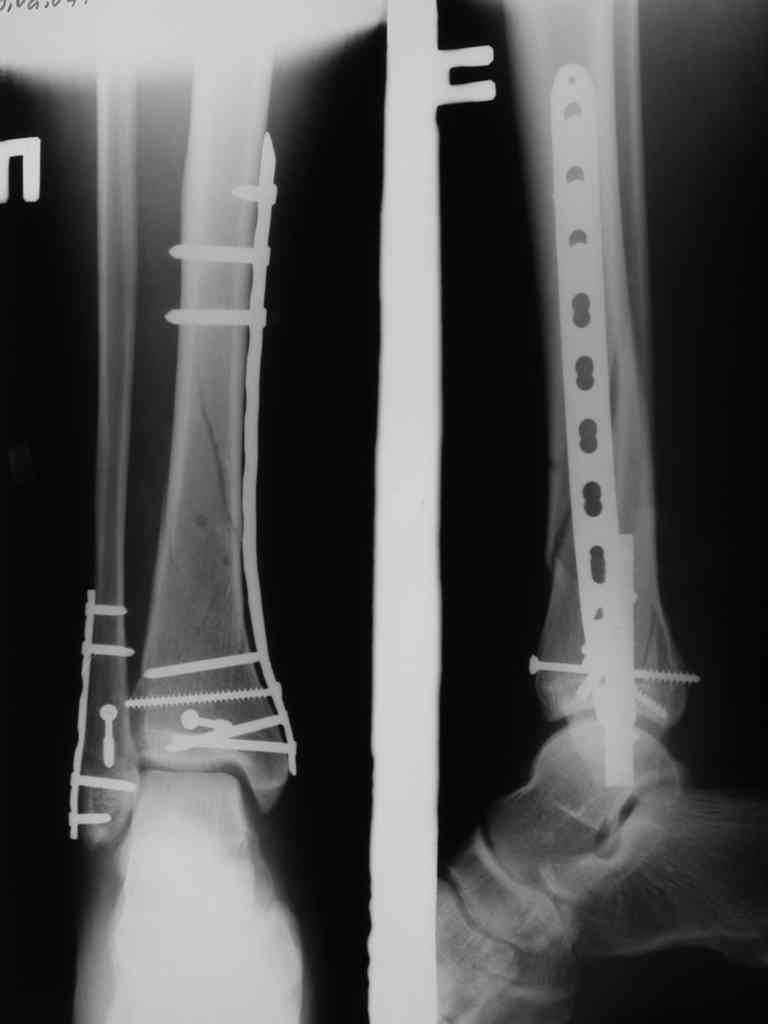

Сегодня прооперировали. Длительность 4-50. Начали как и говорил сверху вниз линейным разрезом - фиксация задне-латерального отломка к проксимальному 2мя винтами, затем "прилепили" к ним передне-медиальный (пришлось повозиться - была интерпозиция и довольно "сложный" винт) - к проксимальному 1 винтом и к задне-латеральному 1 винтом.Кстати на фото видно - у передне-медиального отломка еще осколок в области сустава, несколько смят. Далее началось веселье - второй доступ - задне-наружный к латеральной лодыжке и заднему краю, но оказалось, что задний край больше задне-медиальный (по снимкам было непонятно). Плюс к этому репозиция его мягко говоря сложновата (больной на спине, стол низкий и не поднимается). В общем выставили, фискировали 2мя винтами, на ЭОПе вроде стал, только верх отошел. Латеральную лодыжку заведующий решил интрамедуллярно (не хотел еще винты толкать), сначала 3мм спицей - нестабильно, затем 4мм стержень (не помню по автору) - ОК (кстати в месте перелома мелкая крошка - дефект до 5х7 мм по кортикалу). Ну медиальная лодыжка стандартно - третий разрез - винт 3,5 мм. Визуально все стабильно. На Р-контроле - видна небольшая ступенька заднего края по одному из контуров.

Далее - сейчас нога в пластиковом башмаке (гуманитарная помощь - что-то вроде транспортной иммобилизации - пластик+пневмо), далее заведующий хочет гипсовую повязку до колена. Я предлагаю как иммобилизация аппарат - кольцо - проксимальный метафиз, полукольцо - пятка. По-моему для кожи (оцените на фото), да и для больного лучше. Ваше мнение?

Фото и Р-граммы в приложении

Рентгенограммы

Нельзя ли попросить снимки именно голеностопного сустава. Представлены снимки голени в нижней трети.Сустав фактичеси не виден.

Александр, если вы имеете в виду послеоперационные Р-граммы - то это все что есть. А сустав виден достаточно, чтобы оценить то что есть

Вы представили снимок голени в нижней трети. На сустав луч упал косо, это искажает.

Есть подозрение, что имеется ступенька заднего края, внутренняя лодыжка оттопырена. Взаимоотношения в суставе важнее, чем точная репзиция диафиза.

> Есть подозрение, что имеется ступенька заднего края, внутренняя лодыжка оттопырена. Взаимоотношения в суставе важнее,

> чем точная репозиция диафиза.

Ступенька заднего края и в самом деле вроде есть, но видна по одному из контуров - я о этом писал выше. А лодыжка должна стоять на месте - ставили-то открыто - да и на снимках положение ее правильное.

В боковой проекции - диастаз, 0,5-1мм.

P.S. Все-таки собирать оскольчатый перелом большеберцовой кости просто винтами - несколько неправильно...